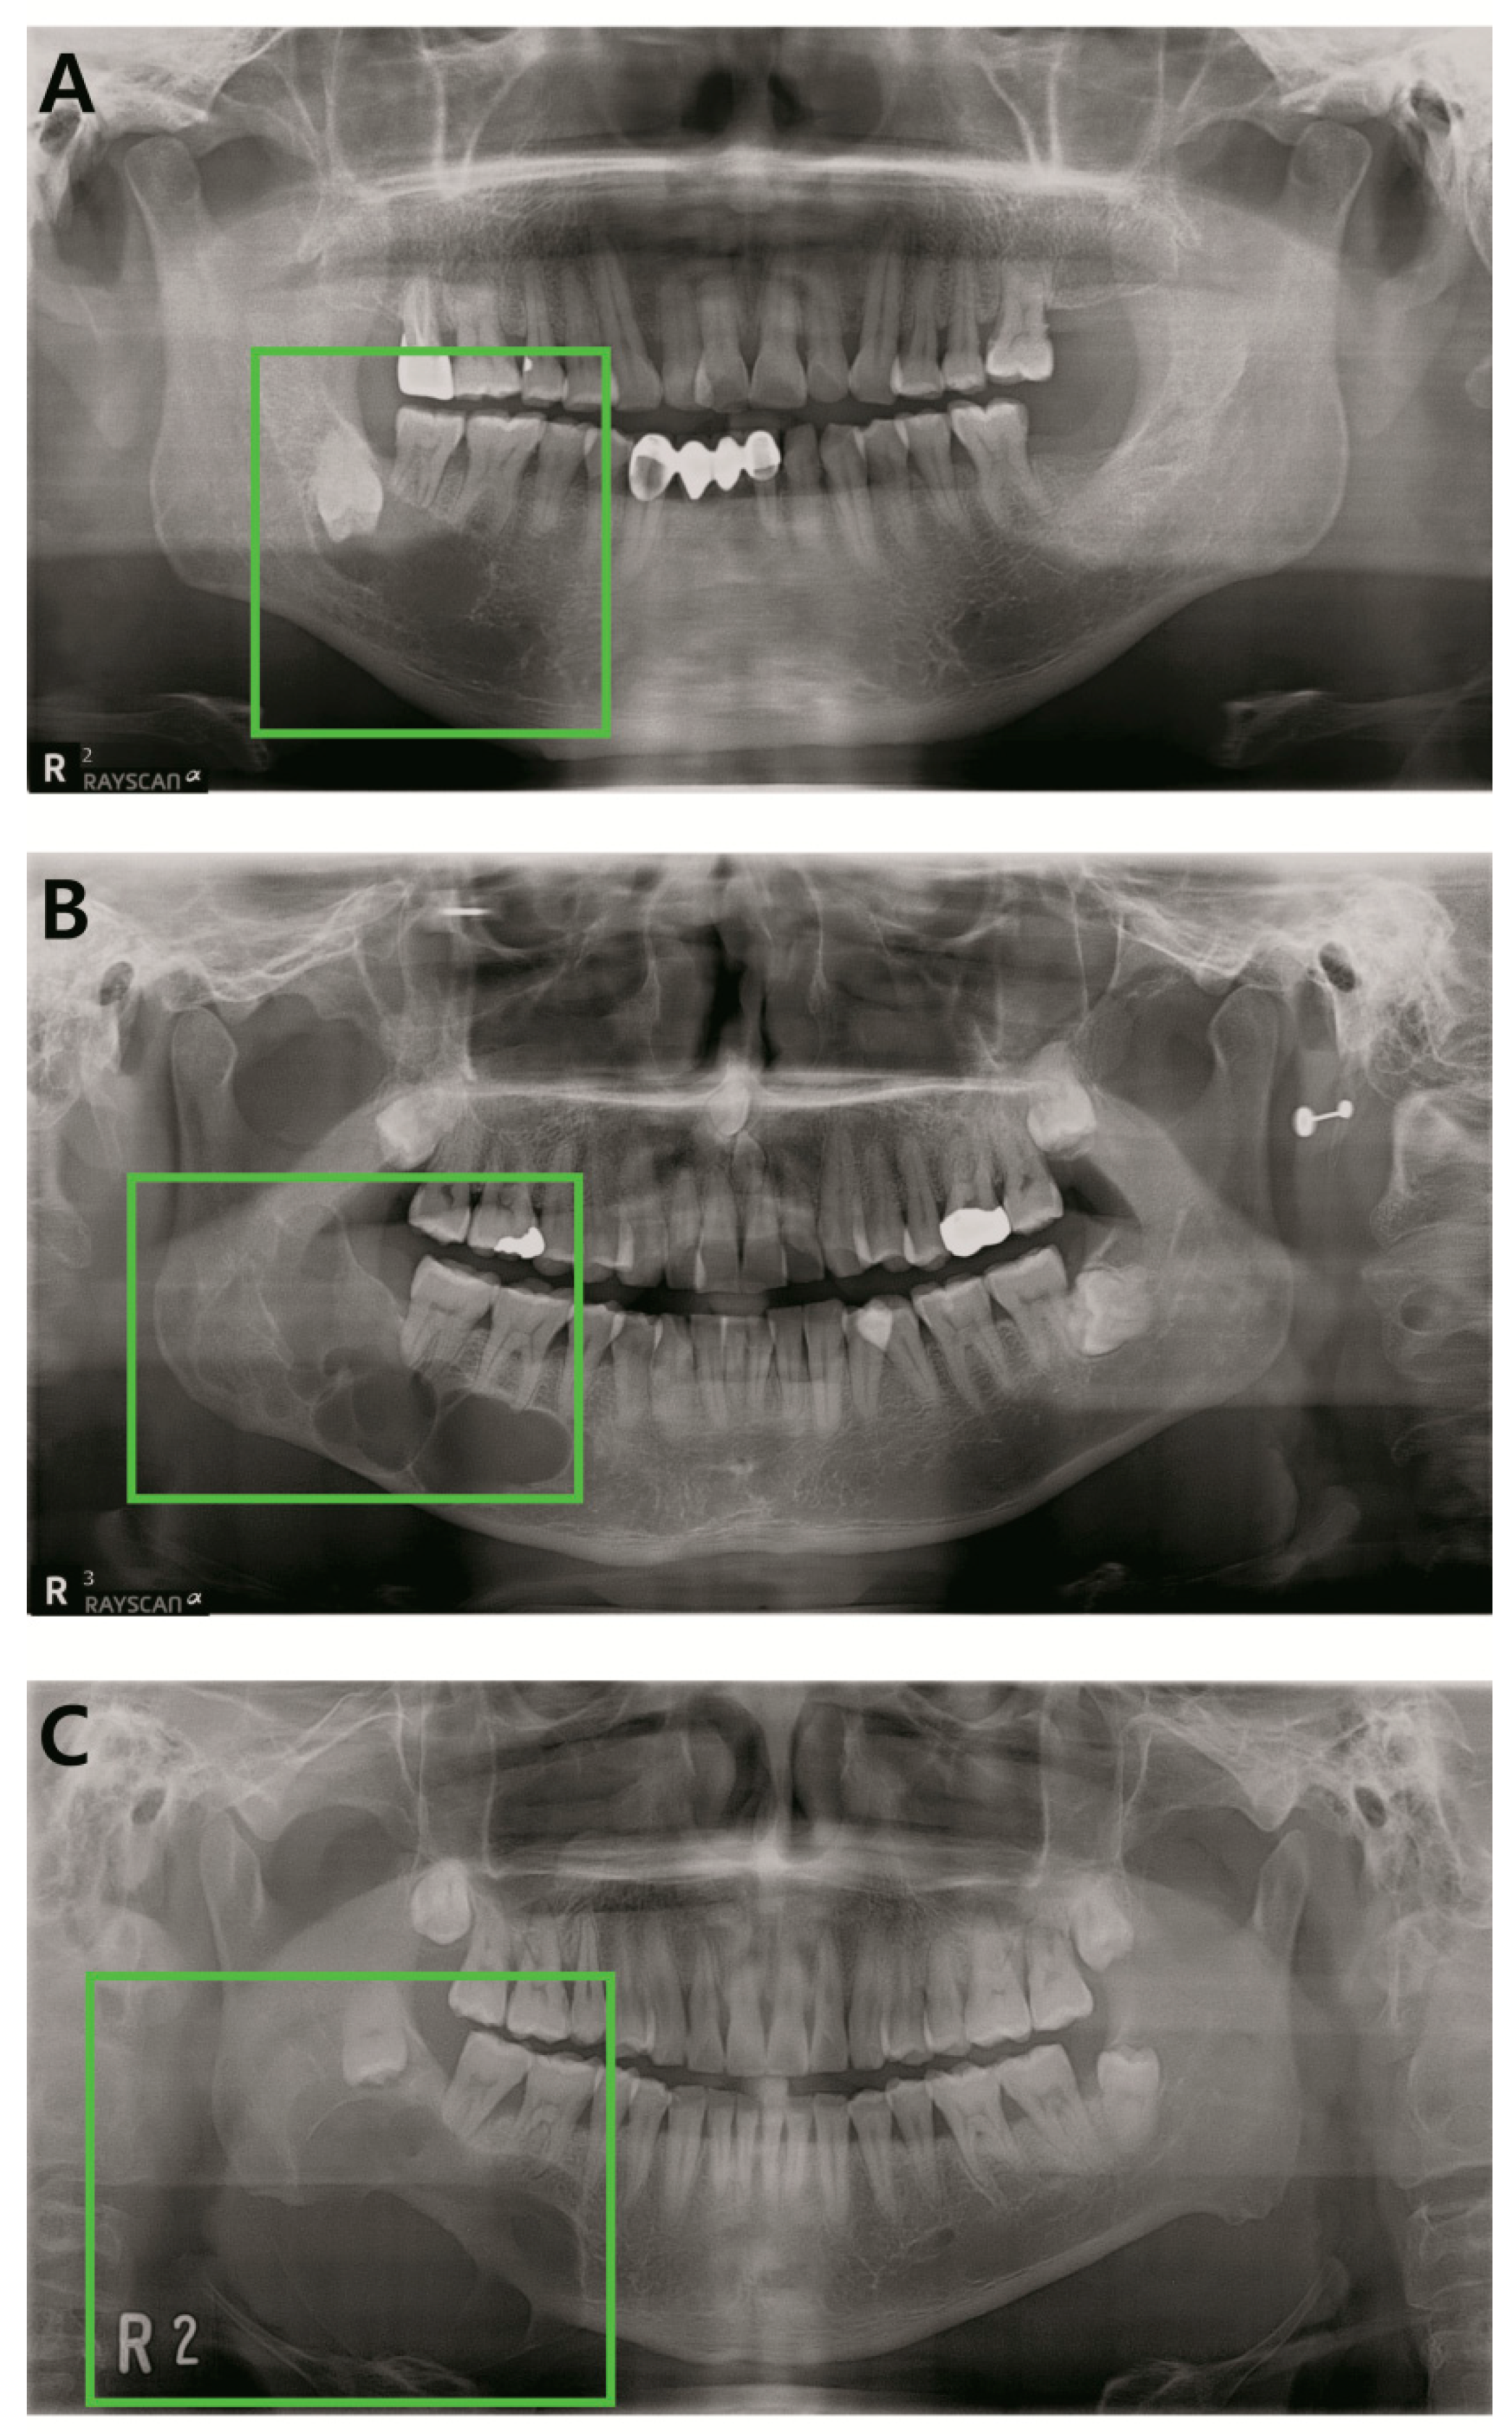

2.2. Annotation of Images

2.3. Pre-Processing and Image Augmentation